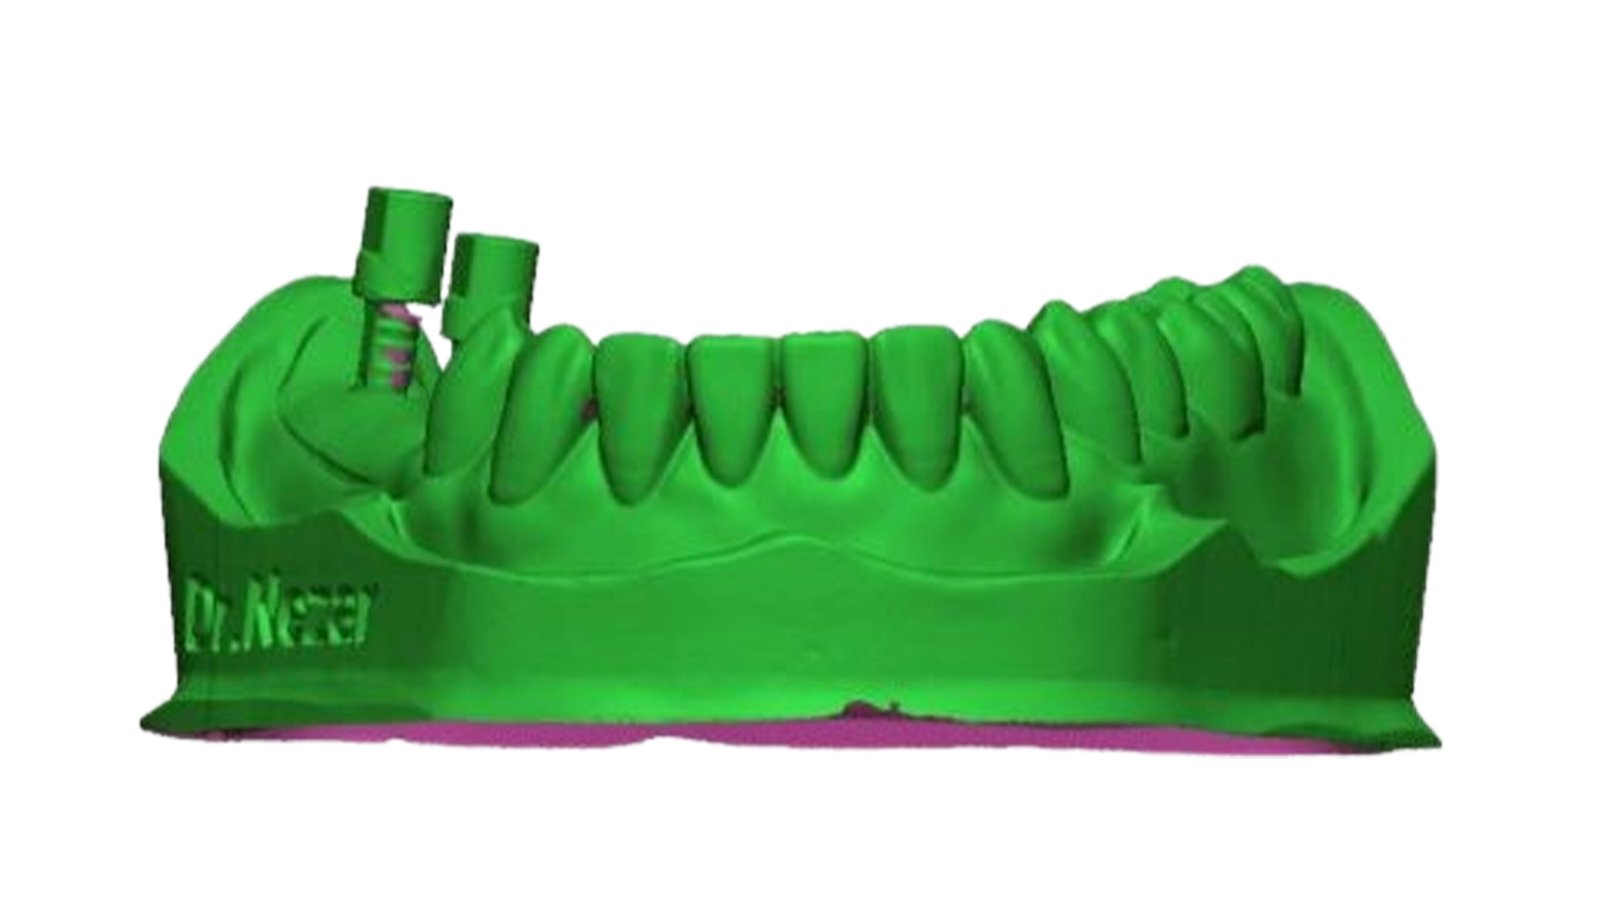

This section specializes in high-precision 3D deviation mapping to compare pre- and post-treatment anatomical or implant-related geometries. Using advanced superimposition and deviation algorithms, we quantify micro-level shifts, deformation zones, and structural discrepancies with sub-millimeter accuracy. These analyses support quality control, surgical verification, and design validation. The resulting deviation heat-maps provide clear, data-driven insights that enhance clinical decision-making and device optimization.